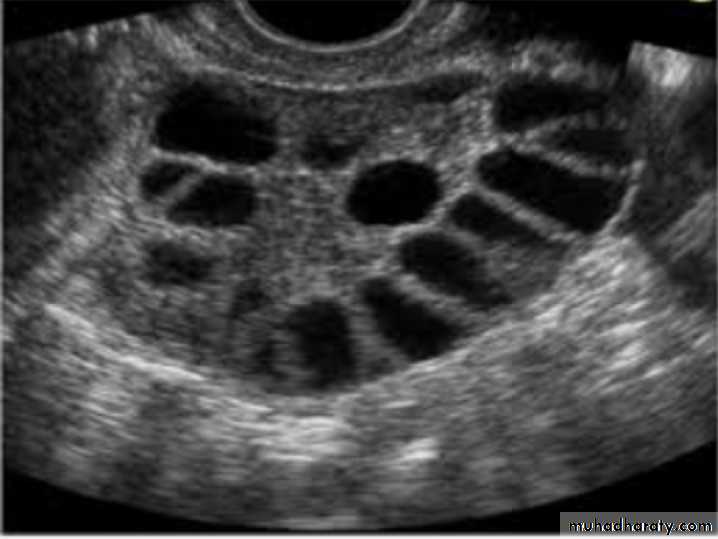

Typical U/S finding in this case : bilateral ovaries containing multiple follicle more than 10 measure 2-9 mm diameter arranged in a neglict apperance with increase stromal thick and overian volum (>10cm3)

U/S:PCOS

PCOS